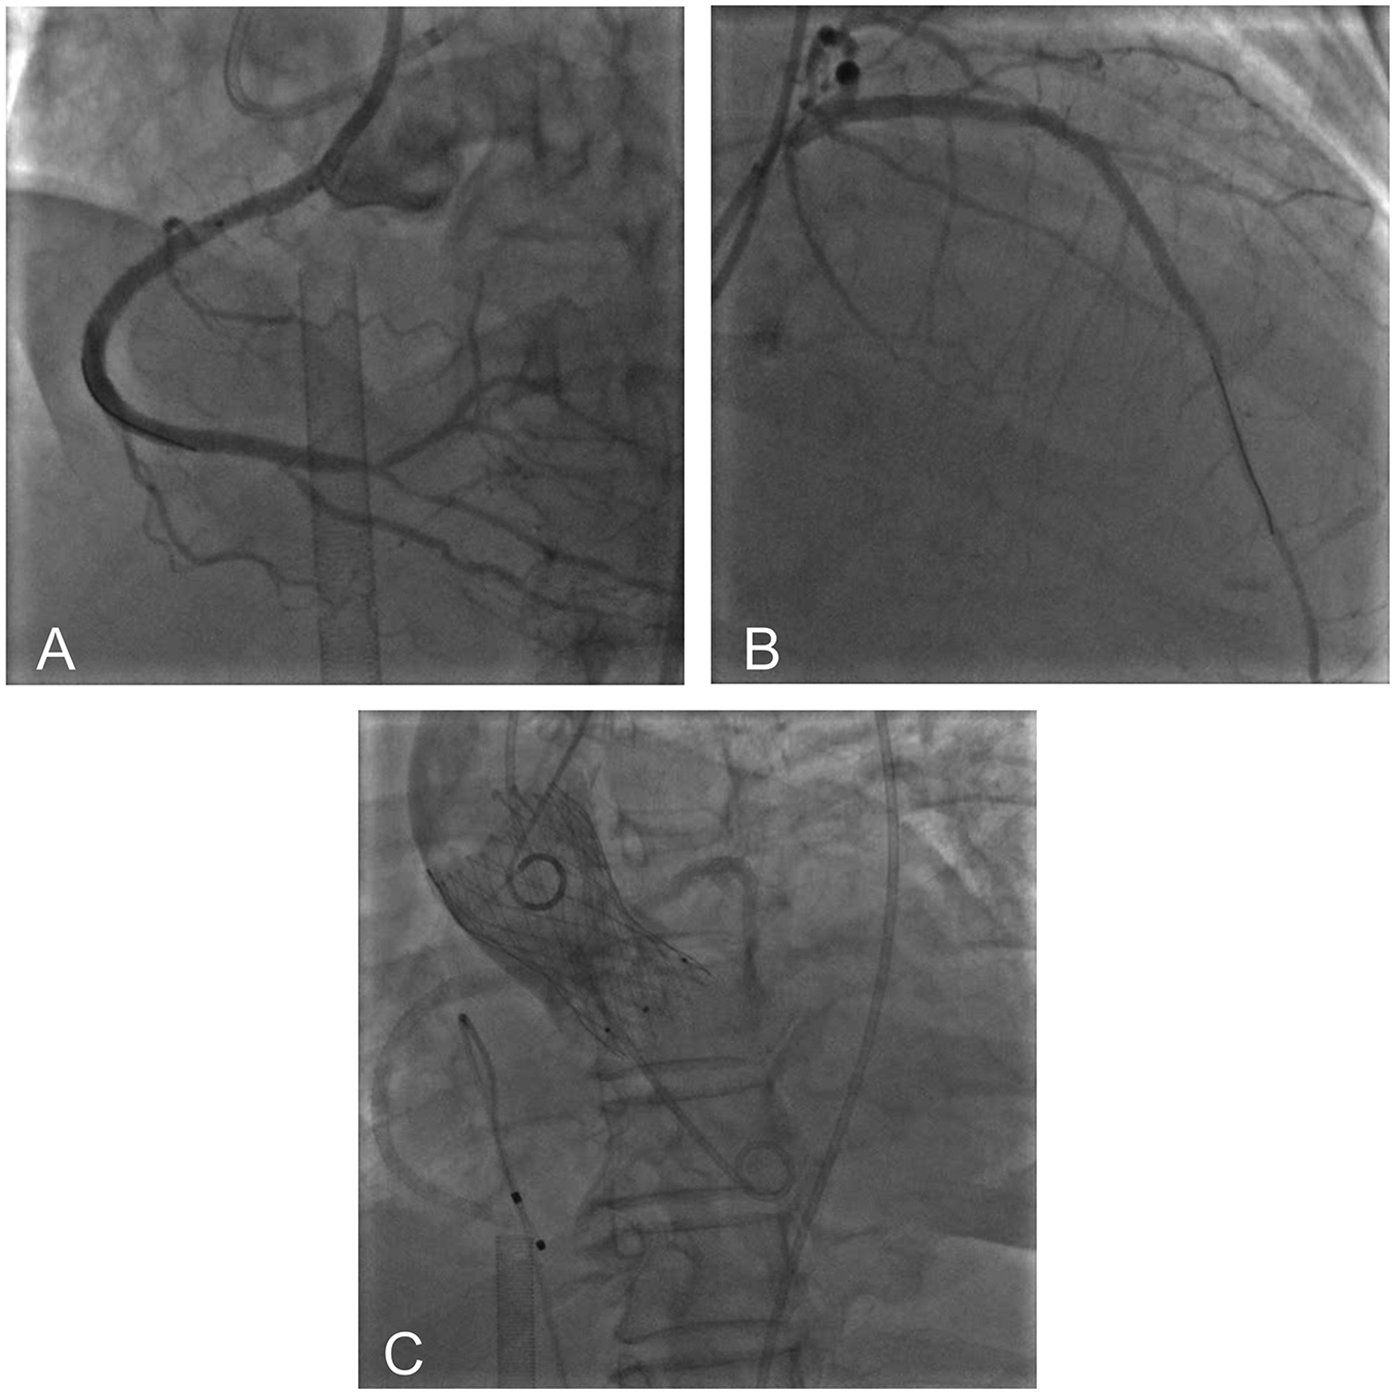

Under light sedation with dexmedetomidine, veno-arterial (V-A) ECMO (Maquet, Getinge AB, Sweden) was successfully inserted using the left femoral venous and arterial access using 21Fr venous cannula and 17Fr arterial cannula. Under dual CAG guidance with a 7F Amplatz Left (AL)1.0 guiding catheter (right femoral access) (Beijing Demax Medical Technology Co., Ltd., China) and a 6F Extra Back-up (EBU)3.5 guiding catheter (right radial access)(Medtronic, Inc.,USA), a Runthrough guidewire (Terumo Co., Japan) was advanced to the RCA acute marginal branch. An ultrasound catheter was used to locate the opening of the occluded segment of the RCA. XT-R guidewire (Asahi Intecc Co., Japan) under the support of Finecross microcatheter (Terumo Co., Japan) successfully recanalized the occluded RCA. Retrograde angiography confirmed the guidewire in the true lumen. After sequential pre-dilation using a 1.5 × 12 mm balloon (Boston Scientific Co., USA), 2.0 × 20 mm balloon (Yinyi Biotech, China), and 2.25 × 13 mm scoring balloon (Goodman Co., Ltd, Japan) at 8–12 atm. Three stents were deployed from distal to proximal: A 2.5 × 38 mm stent (Boston Scientific Co., USA) and two 3.0 × 30 mm stents [Essen Technology (Beijing) Co., Ltd.] (Figure 3A). Afterwards, the stenotic lesion in the LAD was dilated and stented with a 2.75 × 38 mm stent (Boston Scientific Co., USA) and a 3.0 × 25 mm stent [Essen Technology (Beijing) Co., Ltd.] (Figure 3B).

Figure 3

Postoperative imaging showed successful recanalization of RCA (A) and LAD (B) aortic root angiography showed optimal valve positioning with patent coronary ostia (C).